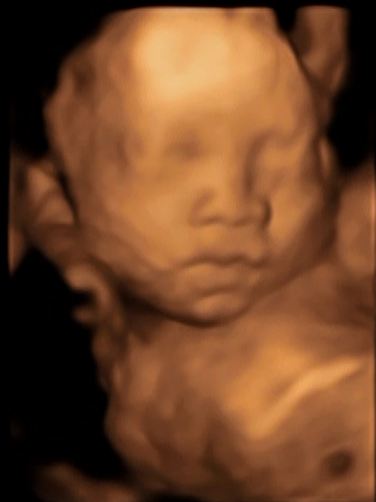

แต่สุดท้าย ก็มีแอบยิ้มให้เห็นเล็กๆ (จุดสีดำที่หน้าผากเป็นเพียงแค่เงานะคะ)

รูปที่เจ็ด เป็นไฮไลท์คะ มียิ้ม อิอิอิ laugh

คุณหมอทายขำๆว่า รูปหน้าเหมือนคุณพ่อ และอาจจะออกมาเป็นอาหมวย เนื่องจากเบ้าตาไม่ลึกและไม่โตมาก หากเป็นเด็กตาโต เงาของเบ้าตาจะโตกว่านี้คะ แม่เกดแอบเคือง ลูกชายก็เป็นอาตี๋เหมือนพ่อไปแล้ว ยังมีอาหมวยมาอีก แม่ออกจะตาโต ไม่มีใครได้ตาแม่เลยยยยย………ฮึ่มๆๆๆ สงสัยต้องมองหน้าญาญ่าบ่อยๆแล้ว (จะทันมั้ยเนี่ย??)